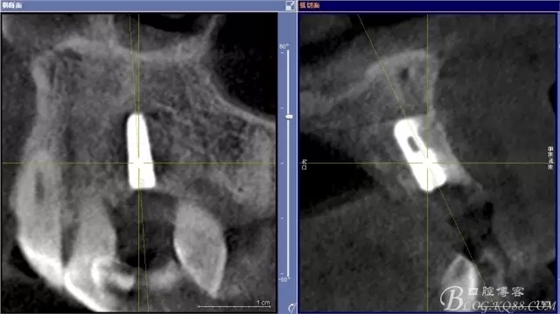

患者、楊xx、男、49歲。主訴:左側(cè)前牙拔除半年,活動義齒修復(fù)四個月,要求種植修復(fù)。??茩z查:21缺失,牙槽粘膜厚度正常。CBCT檢查:高度16mm,寬度7mm.術(shù)前簽知情同意書。

圖1.術(shù)前的CBCT檢查:22缺失。

圖2.CBCT的三維成像及縱剖面、水平面影像

圖11.術(shù)后的CBCT檢查: